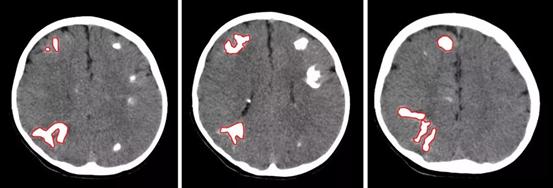

术前CT,红圈标注为不同角度下的右侧脑部4个大结节

通过脑CT及核磁共振检查结果发现闳闳脑内长满了结节点,密密麻麻多达数百个,大的有鸡蛋大小,小的如玉米粒般,布满了整个脑部。在充分研判了患儿病情后,神经外科一病区主任关宇团队决定实施外科手术治疗。